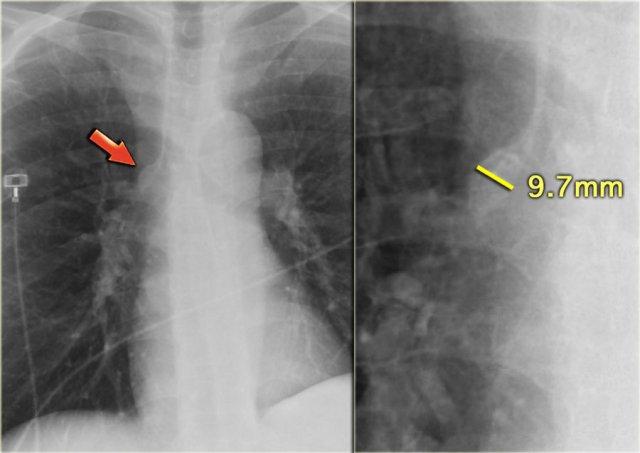

Hình ảnh các mạch máu thùy trên của bệnh nhân trong tình trạng bình thường (trái) và trong giai đoạn suy tim sung huyết (phải). Lưu ý độ rộng tăng lên của cuống mạch máu (mũi tên đỏ).

Bên trái là hình ảnh bệnh nhân có tim to và tái phân phối.

Các mạch máu thùy trên có đường kính > 3 mm (bình thường 1-2 mm).

Lưu ý tỷ lệ động mạch/phế quản tăng ở mức rốn phổi (mũi tên).